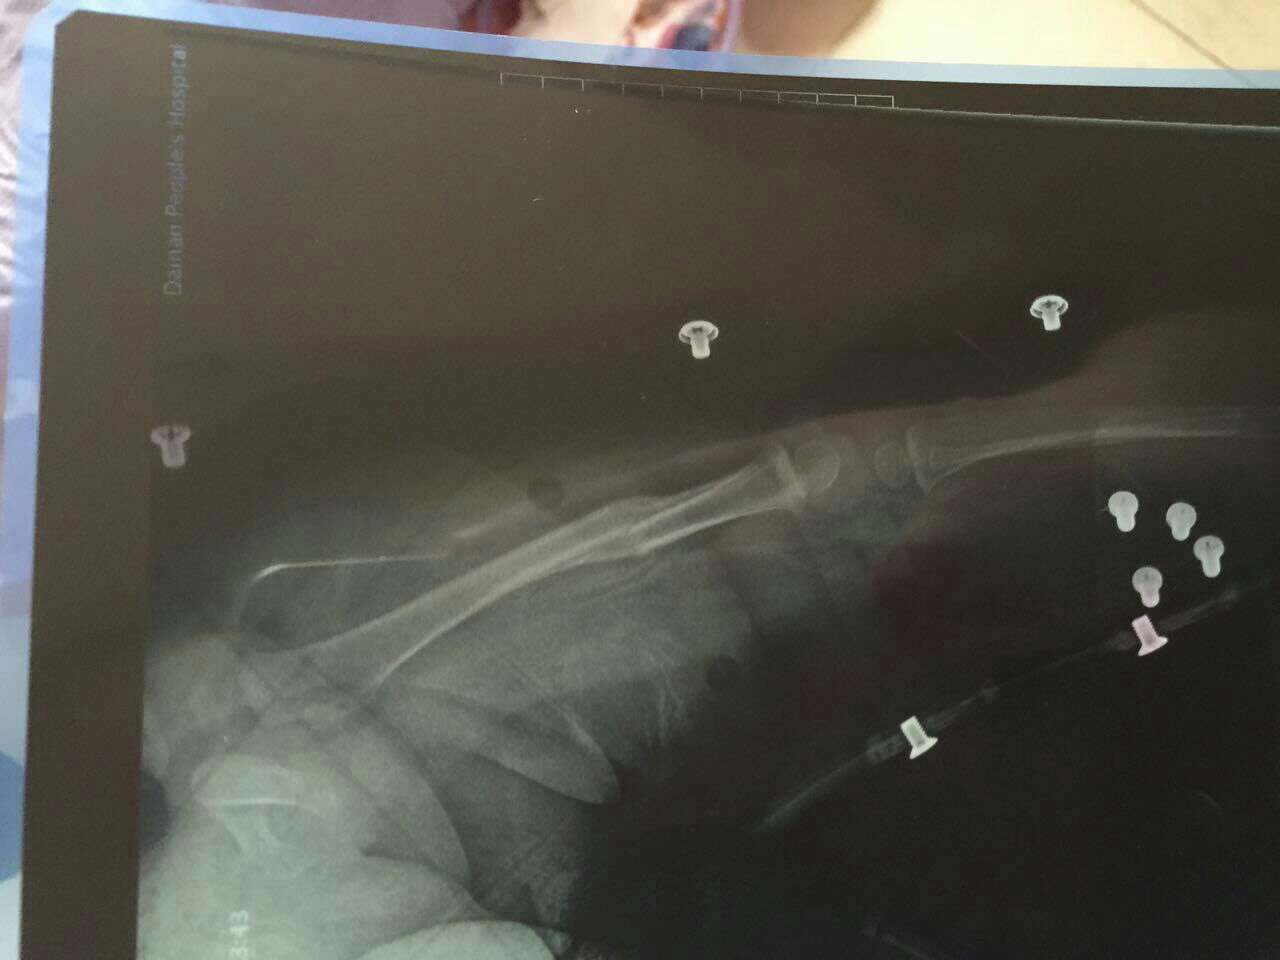

九个月宝宝股骨骨折出大量骨痂形成,可以拿掉支架了吗? 在医院牵引了23天,然后上了支架回来已经22天多,什么时候可以拿掉支架?可以竖着抱吗?什么时候能学走路? 点击展开 匿名用户 2015-01-23 10:53 相关问题 2岁女孩股骨近端骨折后牵引半月dr报告对位对线可,有骨痂影,对以后有没有影响? 我左骰骨骨折 现在手术后已经九个月 我现已上班,是坐着工作,前几天做X线复查,有较多骨痂影,未见内 无骨折症状,带固定支架后骨骺分离